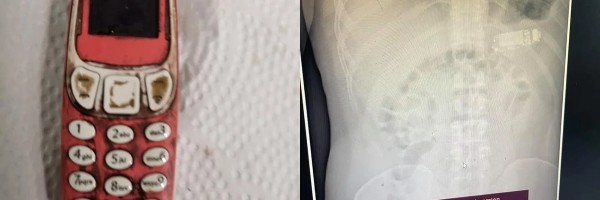

Kosovski Albanac progutao Nokia telefon u komadu

Lekari u južnoj srpskoj pokrajini zahtevali su pomoć vlasti kako bi identifikovali trideset i tri godine starog kosovskog Albanca koji je progutao ceo Nokia telefon i koji se u njegovom stomaku nalazio četiri dana... Pročitaj više